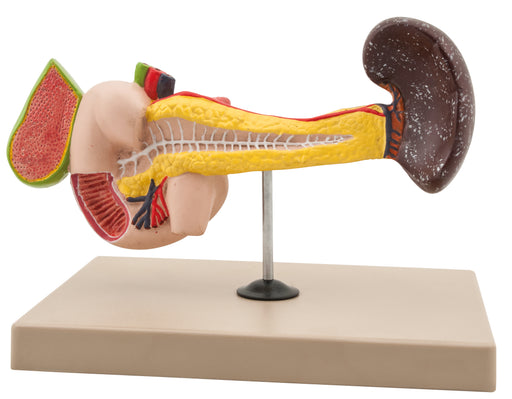

Abdominal Foregut Organ Development Set Of 4

This model showing Abdominal Foregut Organ Development. Mounted on base. Supplied with English Key Card. Size 46 x 40 x 4 cm approx. Weight 2005 g ...